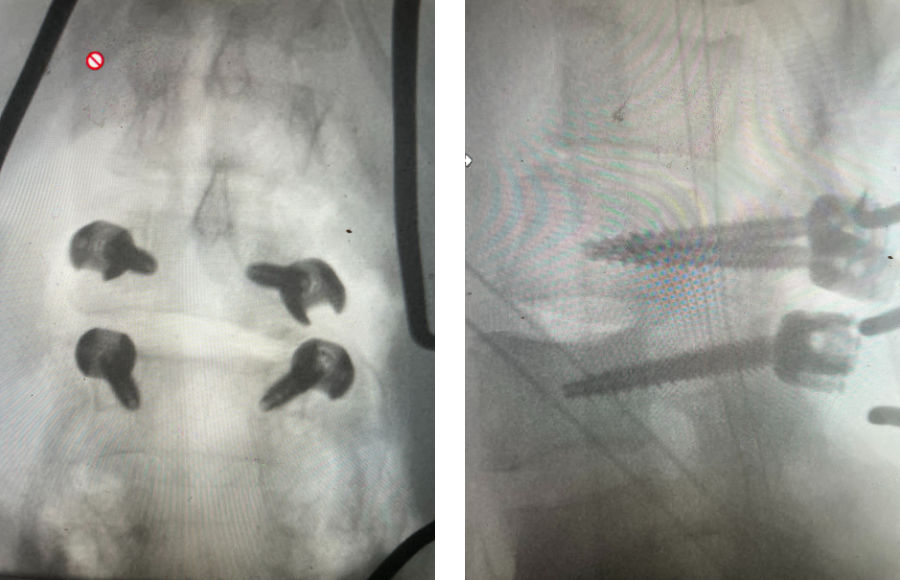

As a spine surgeon you see patients with all body types. Morbidly obese patients pose a particular challenge. Heavy patients who have lumbar spinal stenosis or […]

Patients who are morbidly obese are particularly challenging to manage with spine pathology. When these patients have low back pain and concurrent severe lumbar degeneration, it […]